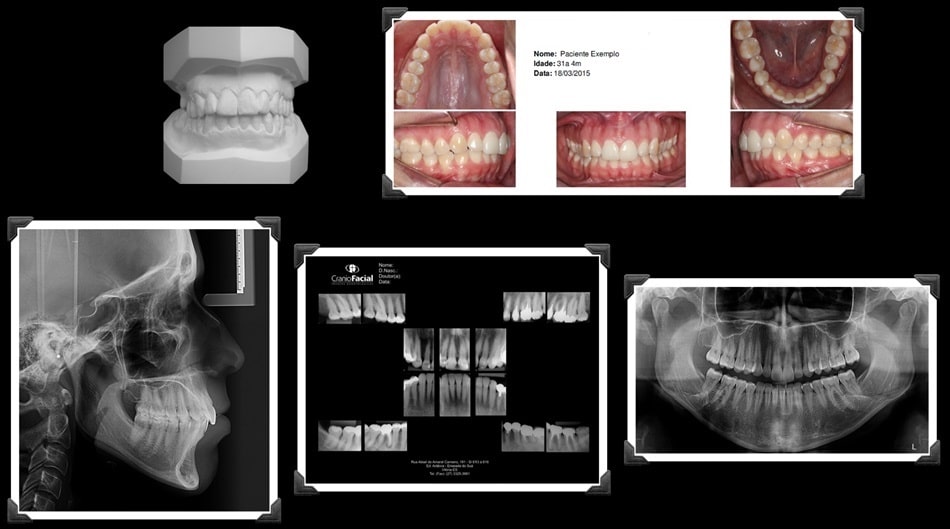

DOCUMENTAÇÃO ORTODÔNTICA

Laudos e Análises Cefalométricas

Fotografias Bucais e Faciais

Modelos de Estudo

Documentações Digitais (Consultório Virtual)